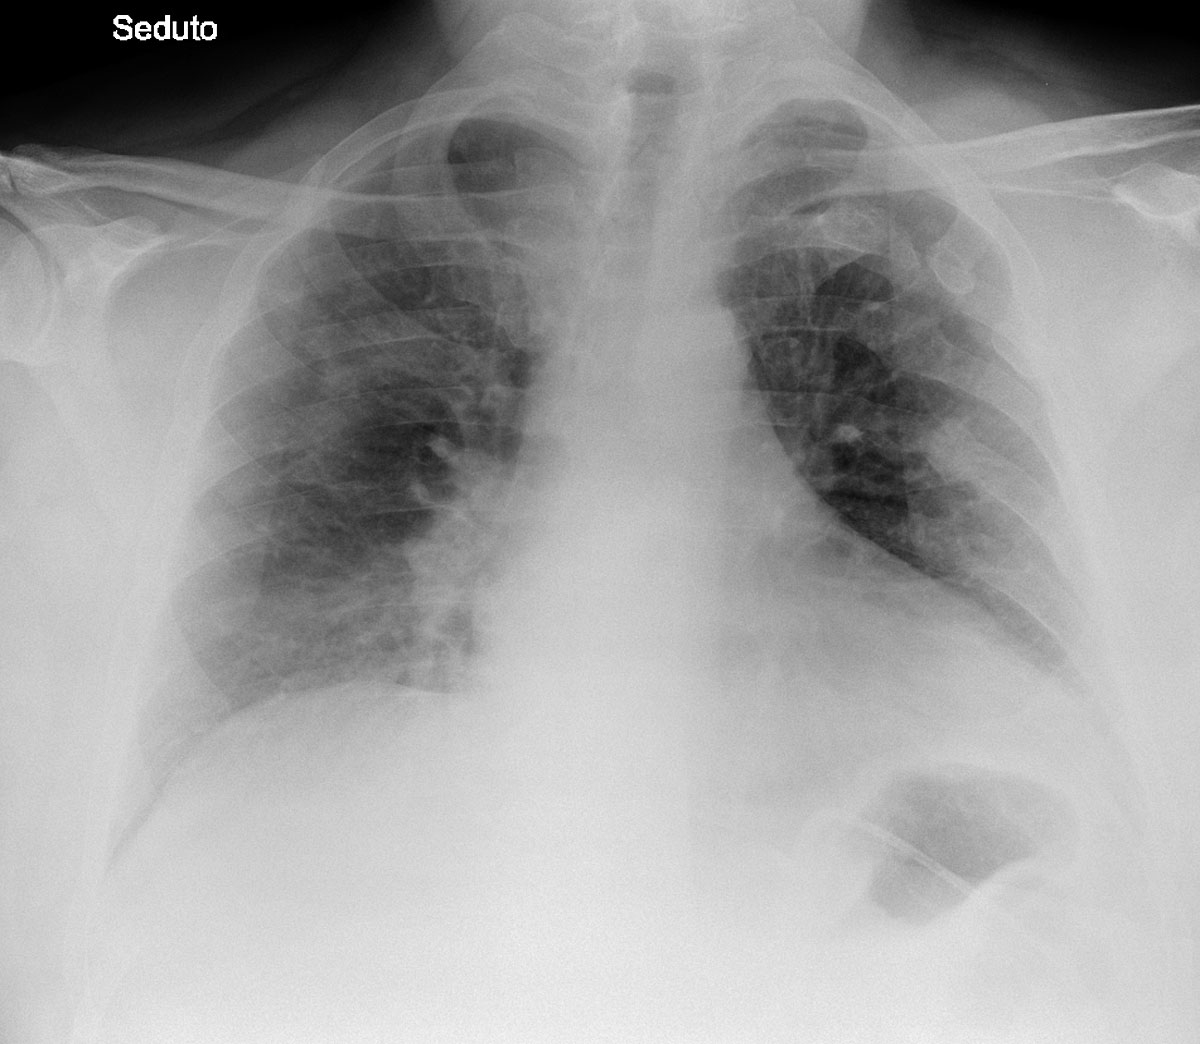

A chest x-ray in anteroposterior projection, with the patient in a sitting position, showed moderate bilateral parenchymal opacities, mostly subpleural and with a mantellar distribution, accompanied by discrete basal pleural effusions (fig. 3).

Figure 3 Chest x-ray of patient 2 on admission, 10 March 2020. Courtesy Ospedale di Sassuolo. Subpleural opacities dominate (see detailed description in the text).